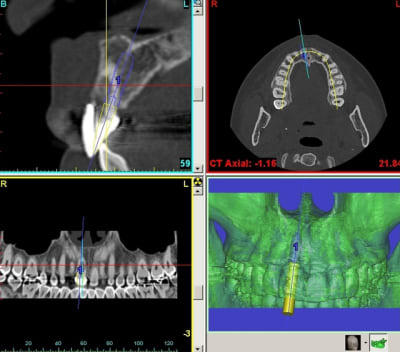

Tiens pour agrémenter! Cet Après midi une extraction implantation. Je n'ai pas oser la mise en charge immédiate si certains l'aurait fait lachez vous.

J'ai fait sauter la table vestibulaire exprès car je ne vois pas comment elle aurait pu etre vascularisée et à part me faire un séquestre osseux et des ennuis j'ai reconstruis.

Regardez les images;

Si certains n'auraient pas extrait argumentez pour traiter en palatin et la felure englobé par le granulome m^me si ce n'est pas mis en évidence sur le scan.

En plus vous voyez le nouvel implant Leone et son indication majeure, c'est vrai que sa mise en place est super aisée, surtout comme celà en palatin.